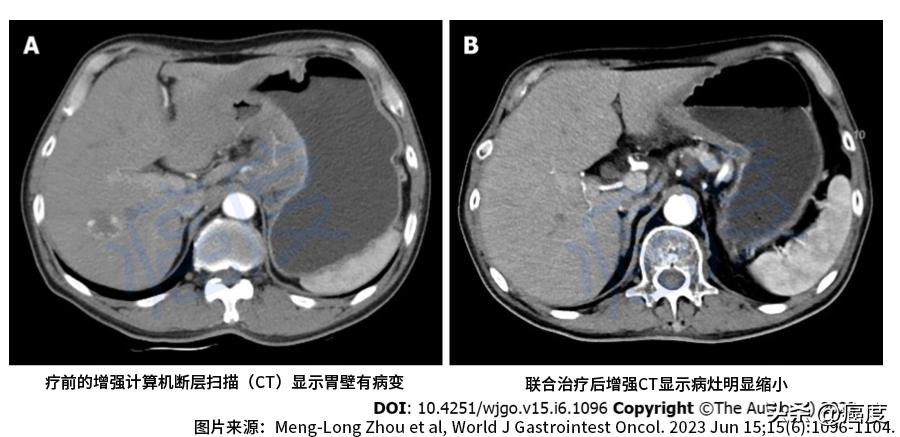

医生在给患者做检查的时候发现其脸色苍白,表现为贫血。左侧锁骨上区可触摸到肿大的淋巴结,但是腹部和直肠指检没看到异常的情况。肿瘤标志物都在正常的范围之内(肿瘤标志物不敏感)。但是胃部增强CT扫描可看到胃体壁增厚,胃周围、肝胃间隙、肺门区、腹膜后有肿大淋巴结,后面的PET-CT检查证实肿瘤已经转移。胃镜检查确定为胃癌。相应的分子检测指标是:微卫星稳定型、HER2两个+(弱阳性,但FISH验证为阴性),二代基因测序证实TMB的数值比较低,具体数值为5.98M/Mb。

治疗前后的影像学检查对比

治疗一个月之后,患者消化不良、黑便明显缓解,胃部增强CT扫描显示胃壁厚度减少,对示踪剂的吸收也降低,总体评估为部分缓解PR。